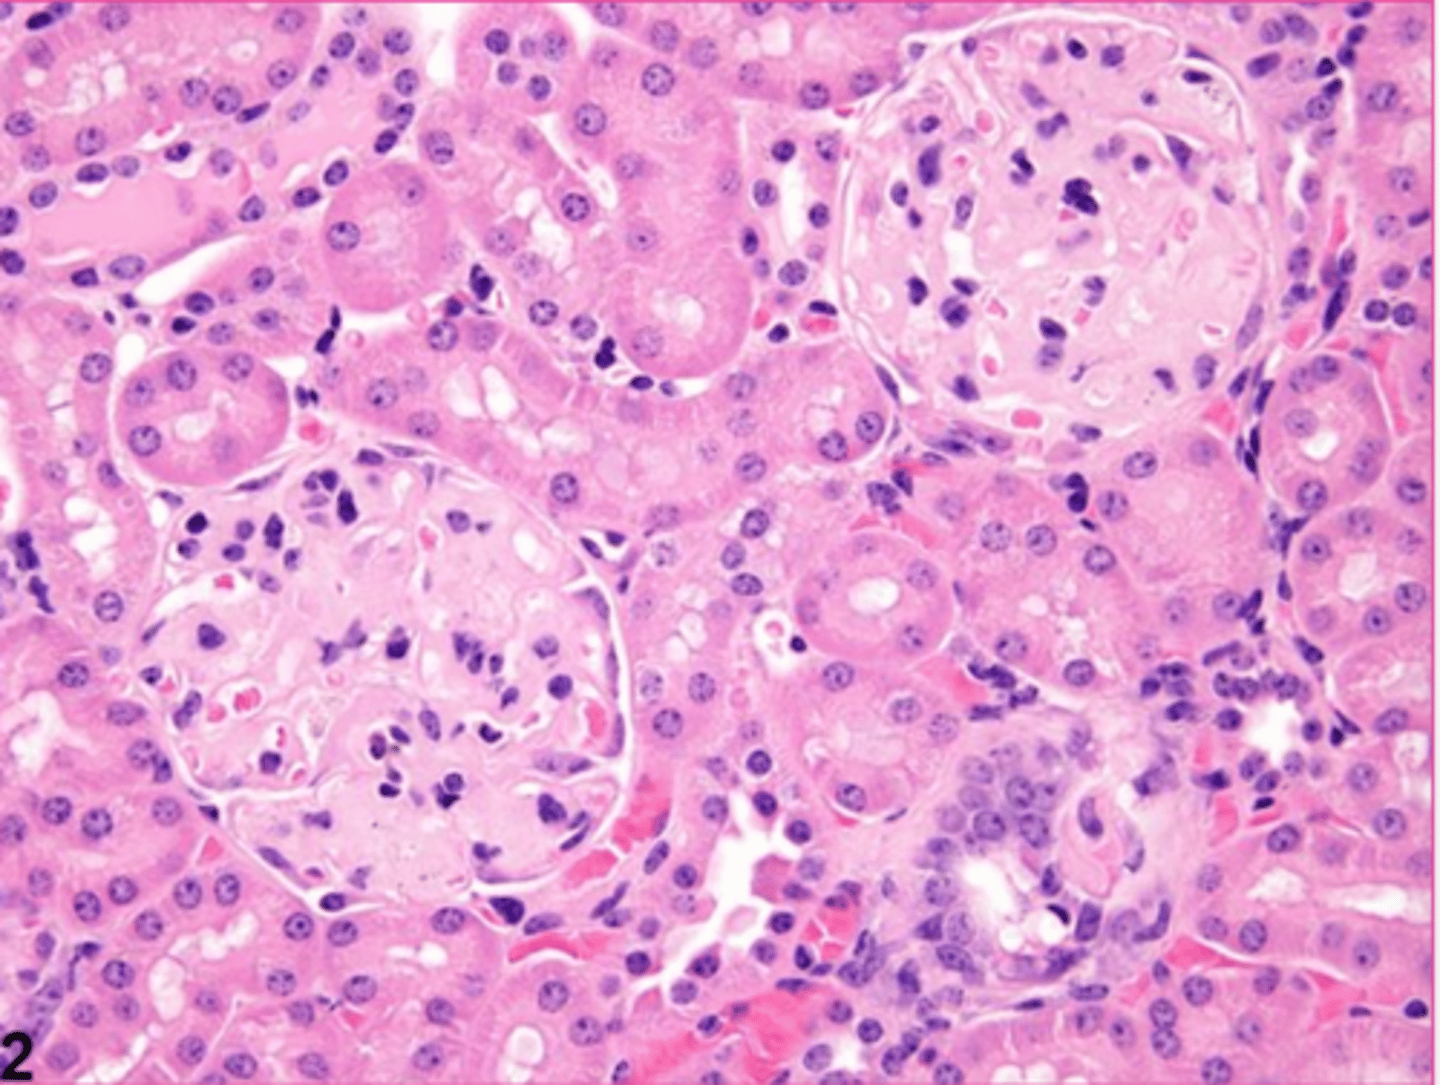

amyloid

describe the extracellular accumulation